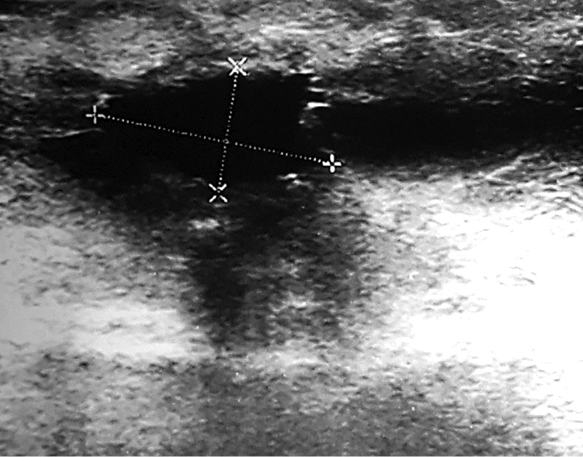

Fig. 1. The lesion was seen on ultrasound image

During physical examination a 2 cm hard, not tender, with ill-defined margins lump in the upper inner quadrant of the right breast has been found. There was no nipple retraction, discharge or skin change. A breast ultrasound showed a 1.24x0.85 cm suspicious ill-defined hypoechogenic lesion at 1 o’clock position of the right breast (Figure 1). Mammogram revealed a local hyperdense zone in the right breast (Figure 2). Histopathological examination of the tumour core biopsy material revealed desmoid type fibromatosis. The patient underwent wide local with clear margins excision of the lesion. Histopathological examination of surgical material confirmed desmoid type fibromatosis (Figure 3). Tumour was poorly demarcated, composed of spindle-shape myofibroblasts arranged in long sweeping fascicles. There was no mitotic activity. Immunohistochemical findings of the mass showed a focally positive reaction with beta-catenin, and a negative reaction for CD34, Desmin, CK. The patient did not require any adjuvant treatment. There was no recurrence after two years of follow-up.

Clinically breast fibromatosis presents as firm, painless mass [4, 8]. Nipple, skin retraction may be seen [2, 4, 8]. On ultrasound images, desmoid tumour typically appears as hypoechogenic, ill-defined mass [1, 8]. In our case, tumour also was firm, not tender, with echoscopically seen ill-defined margins.